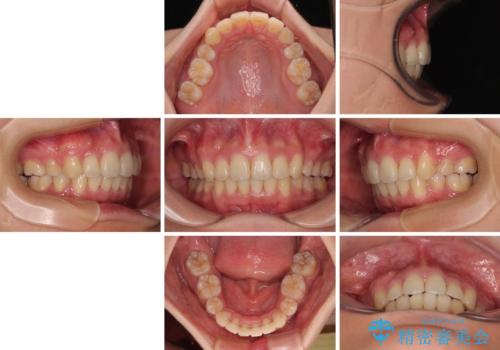

全顎的なデコボコと口元の突出感 ワイヤー装置での抜歯矯正で整った口元に

前歯の突出感がなくなり、仕上がりには大変満足していただけました。

想像以上に咬合力が強く、抜歯したスペースを閉じきるまでに長期間を要することとなりました。